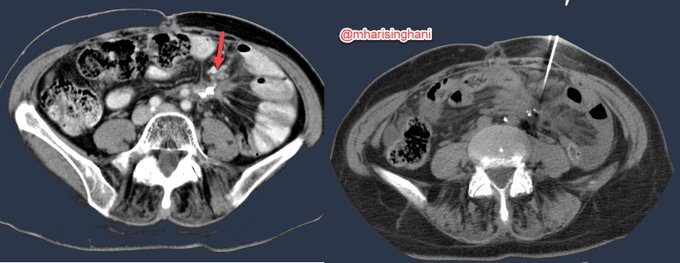

Ventral hernia with primary epiploic appendagitis